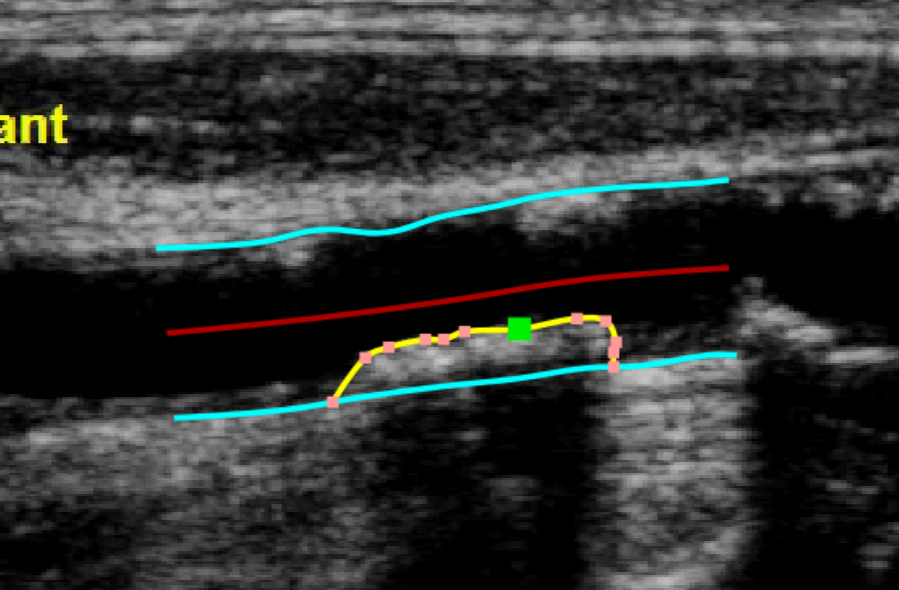

The Trace borders button is used to manually trace the borders of the vessel. The user has to trace point-by-point the vessel edges and the software interpolates them. It is possible to modify the points by dragging them, as shown in the following picture.